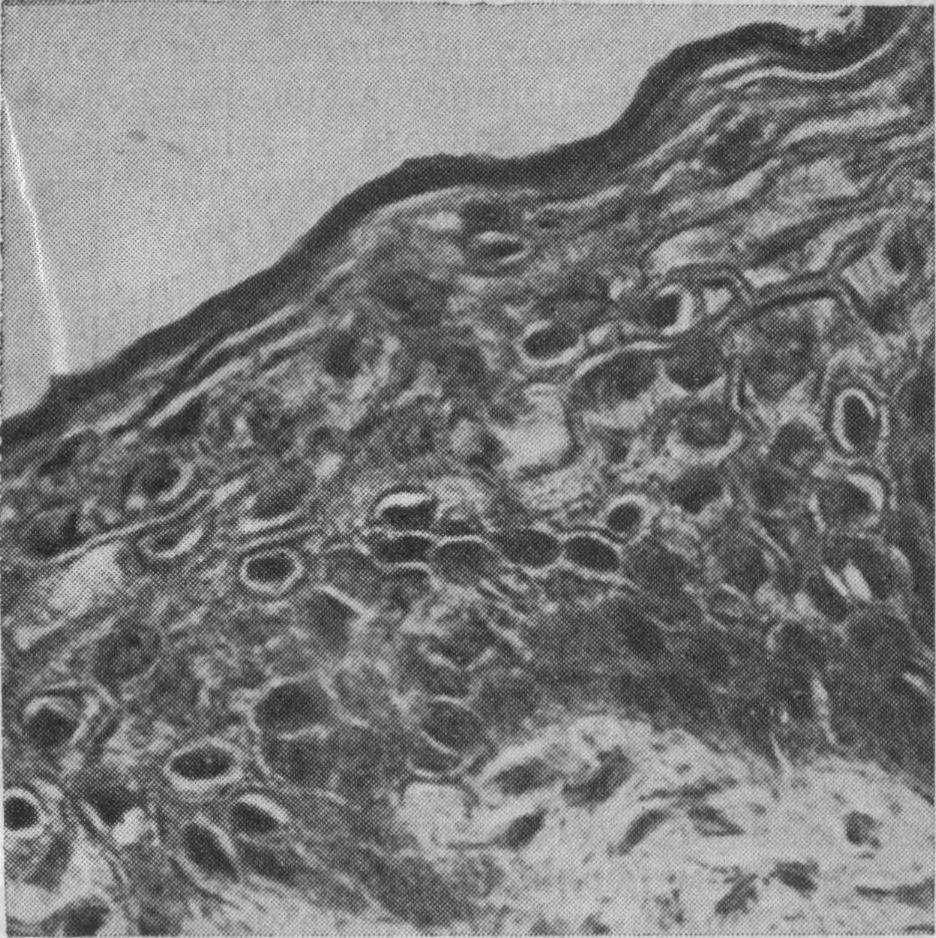

Рис. 11. Паракератоз в эпителиальном пласте слизистой оболочки.

твердого неба.

7-месячный плод. Окраска гематоксилин-эозином. Х400 (Реброва М. А.).

Особое внимание было обращено на состояние поверхностной части эпителия, так как мнения авторов о наличии рогового и зернистого слоев расходятся. По нашим данным, поверхностные ряды клеток эпителия у плодов (рис. 11) и большинства новорожденных находятся в состоянии паракератоза и лишь в некоторых случаях наблюдается истинное ороговение. Явления паракератоза отмечала и Н. Дамова (1964), но ороговения не выявила.

У детей в возрасте 1—6 мес обнаруживаются признаки паракератоза поверхностных клеток эпителия, в цитоплазме их отмечается большое количество крупных гранул кератогиалина. Это указывает на постепенное нарастание процесса ороговения и у детей дошкольного возраста на всем протяжении слизистой оболочки твердого неба выявляется чередование участков паракератоза с истинным ороговением.